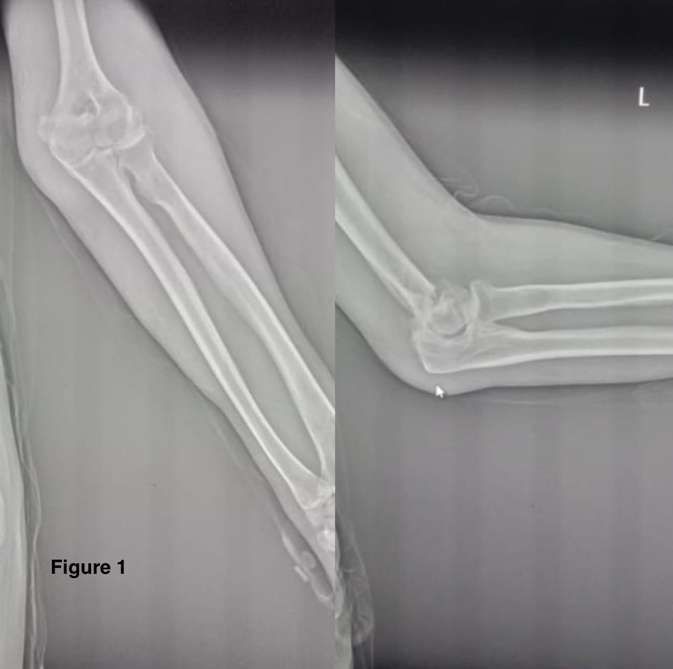

Unorthodox Ulnar Nerve Arborization at the Distal Metadiaphyseal Humerus: An Insight into the Neuroanatomical Oddity and its Surgical Implication

Meet Ajay Mehta , Avik Kumar Naskar , Himanshu Pradeep Ganwir , Vikas Anandrao Atram ………………………………p.65-68